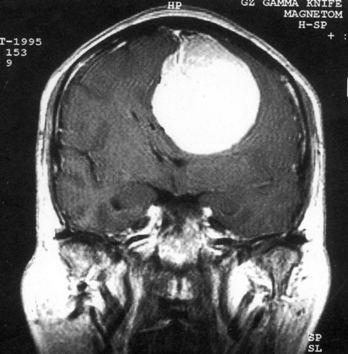

问题 病历摘要:??患者,男,40岁。发作性左下肢抽搐1年余,每次发作3~5分,每周发作1~2次。每次发作后感左下肢乏力,约半日后可自行恢复。既往身体健康。体检:神清,头顶部偏右有局限性骨性隆起(1.5×1.5cm),左鼻唇沟稍浅,伸舌居中。感觉、运动无明显异常。左浅反射减退,左下肢腱反射稍亢进,左Babinski征(-)。 下列关于脑膜瘤的叙述哪些是错误的?